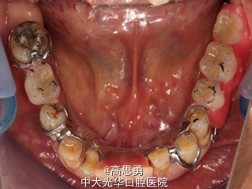

检查(包括专科检查及辅助检查): 1、全身状况良好,无全身系统性疾病,自主行动能力正常。精神心理状态无异常。 2、颌面部左右对称,面部比例协调,面部正面形态尖圆形。颞下颌关节运动无异常,开口型无异常,颞下颌关节无弹性,无压痛。 3、口内黏膜未见瘢痕,舌运动无异常。唇颊系带附着无异常,唾液分泌无异常。 4、牙龈正常,无肿胀无瘘管。 5、口内检查: #32近中移位约1mm,无明显倾斜 #44远中移位约2mm,向缺隙侧倾斜,伸长约1mm 其余缺牙间隙正常 全口牙龈退缩至根颈1/3,牙龈无肿胀无瘘管 上颌缺牙区牙槽嵴无明显吸收、下颌缺牙区牙槽嵴吸收呈低平刃状 口腔卫生状况欠佳、全口牙石多 11 12 13 14 15 16 17 21 22 23 24 25 26 27 视 存 存 存 缺 缺 缺 缺 存 存 存 缺 缺 缺 存 探 - - + - - - - - - - - - - - 叩 - - + - - - - - - - - - - - 松 - - I° - - - - - - - - - - - 楔 O O O - - - - O O O - - - - 31 32 33 34 35 36 37 41 42 43 44 45 46 47 视 缺 存 存 存 缺 缺 缺 缺 存 存 存 缺 缺 存 探 - - - - - - - - - - - - - - 叩 - - - - - - - - - - - - - - 松 - - - - - - - - - - - - - - 楔 - - O - - - - - O O O - - - 根尖X片示:13 根尖部阴影,牙颈部硬组织部分缺损 转诊牙体牙髓科后复诊 修复科第二次就诊口内检查: 11、12、13、21、22、23、33、42、43、44牙颈部见黄色充填物 13 探(-)、叩(-)、松(-),HE面见白色暂封物 口腔卫生状况尚可、牙石少,其余牙叩(-)、松(-) 根尖X片示:13 根尖部阴影,根充可 其余同前

诊断: 1、牙列缺损(上颌肯氏II类I分类,下颌肯氏II类II分类) 2、#13慢性根尖周炎 3、#11、#12、#13、#21、#22、#23、#33、#42、#43、#44楔状缺损 4、慢性牙周炎 治疗计划 1、#13转牙体牙髓科做RCT 2、转牙体牙髓科对#11、#12、#13、#21、#22、#23、#33、#42、#43、#44楔状缺损 充填治疗 3、转牙周科进行牙周洁治 4、择期RPD修复 备选修复方案: 1、#13RCT后截冠后,上下颌覆盖义齿修复; 2、#13RCT后冠修复,上下颌可摘局部义齿修复; 3、#13RCT后树脂充填,上下颌可摘局部义齿修复; 4、#13拔除后,上下颌可摘局部义齿修复。 患者意愿:患者希望尽量保持#13的天然形态,要求费用尽量低,但能恢复正常咀嚼功能。 最终治疗方案:根据患者的年龄、身体状况、治疗周期、经济状况,患者最终选择方案5,即#13RCT后树脂充填,上颌结合卡环式可摘局部义齿修复;下颌可摘铸造支架式局部义齿修复。 治疗过程: 1、临床检查和#13树脂充填 对患者进行全面的口腔检查,用Z350树脂充填#13,调HE,抛光。 2、研究模型 调拌藻酸盐印模材料于2号成品托盘上取上下颌研究模,灌注石膏模型,研究分析、制定治疗计划,并制作个别托盘。 3、基牙预备 对#13近中、#23远中、#27近中、#34近中、#47近中常规制备支托凹,抛光。 4、工作模型 调拌藻酸盐印模材料于个别托盘上。做一定的边缘整塑,取上下颌研究模,灌注石膏模型。 5、试戴支架 检查支架的就位、固位可,无翘动,调HE,抛光,用蜡堤取颌位关系,上颌架,排牙,比色C4。 6、试排牙 检查义齿的就位、固位可,无翘动,观察人工牙的咬合状况,尖窝接触良好,正中颌位能重复,患者无诉不适,面容自然,外观满意。送加工厂充胶制作最终修复体。 7、试戴 检查义齿的就位、固位可,无翘动,咬合关系正确,利用咬合纸检查,上下颌尖窝接触均匀全面,抛光,患者表示满意,嘱注意事项,定期复诊。